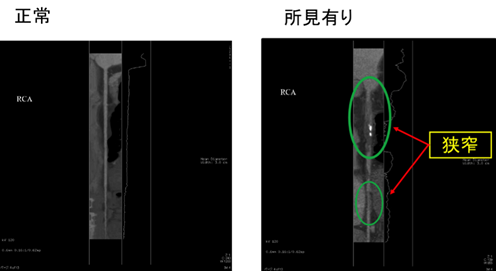

画像の再構成をおこなって血管を真っ直ぐに伸ばすと下記のようになります。

先ほどと同様に右の画像の血管の一部は造影剤が流れておらず、狭窄しているのがわかります。また白く光っている部分は石灰化になります。